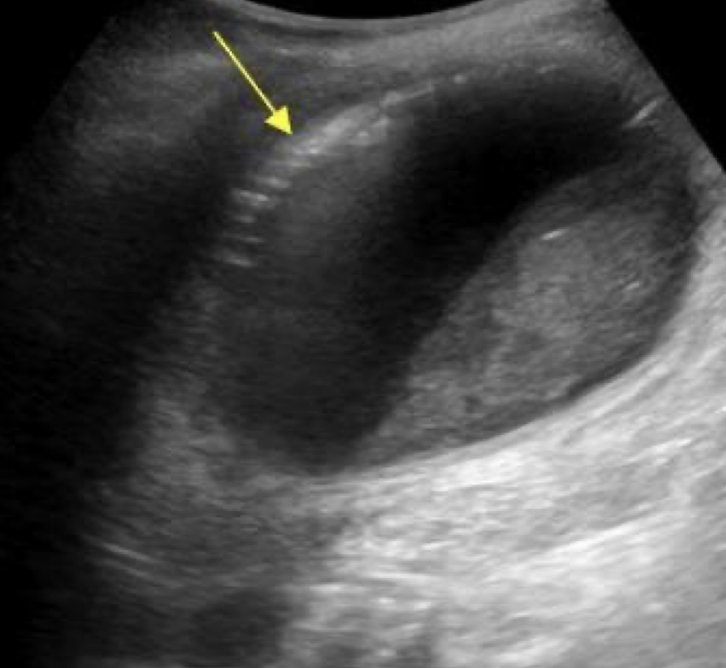

cholecystectomy

removal of GB —>

sphincter of Oddi loses tonus

bile flows freely into duodenum (biloma)

extrahepatic bile ducts dilate, up to 1 cm

??

biloma